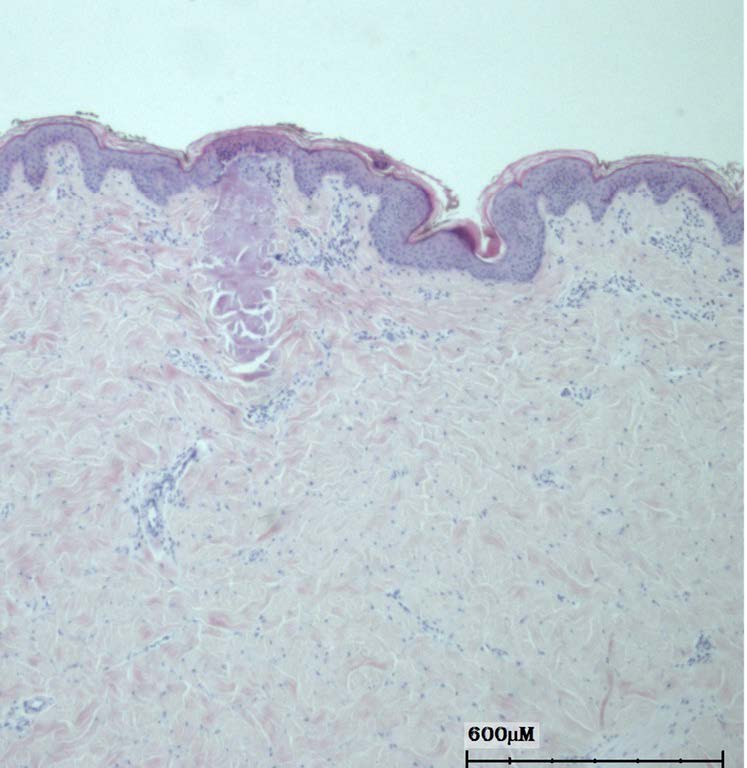

Fully ablative resurfacing removes the entire surface layer of skin across the treated area. The laser energy vaporises the outer layers of tissue and heats the deeper dermis, which stimulates collagen remodelling during healing.

Because the entire surface is treated, the skin must regenerate a new epidermal layer during recovery.

Fractional ablative resurfacing works differently. Instead of removing the entire surface layer, the laser creates thousands of microscopic columns of treated skin while leaving surrounding areas untouched.

These untreated areas act as reservoirs of healthy tissue that help the skin repair itself more quickly.

Non-ablative treatments heat the deeper layers of the skin without removing the surface layer. Instead of vaporising tissue, these treatments deliver controlled thermal energy into the dermis to stimulate collagen production.

Because the outer skin remains intact, recovery time is usually minimal.